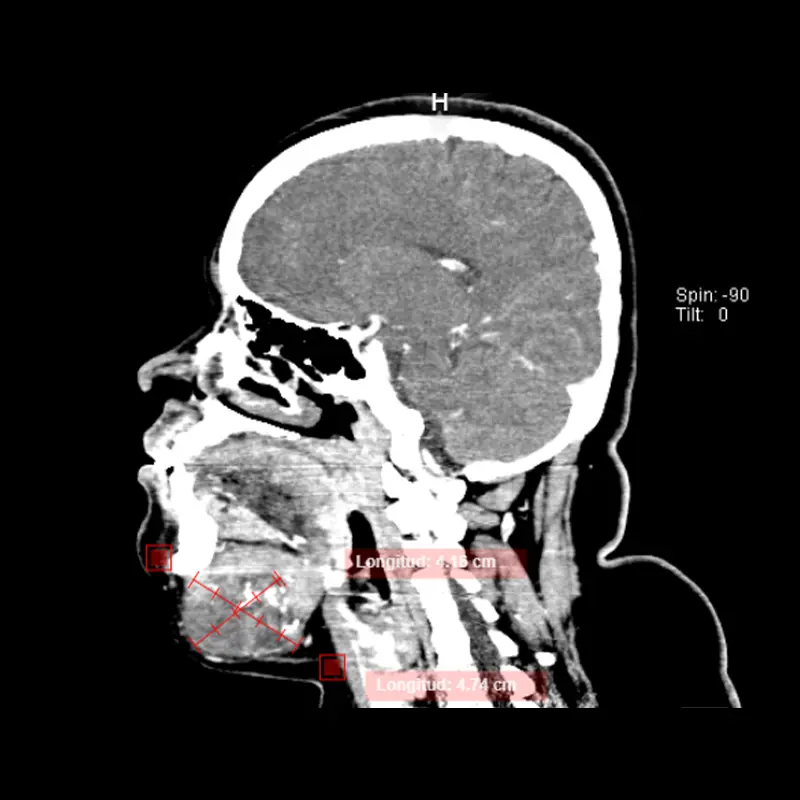

Cirugía ortognática (asimetrías faciales)

Corrección quirúrgica de deformidades óseas en mandíbula y maxilares para mejorar estética, mordida y respiración.

La cirugía ortognática, del griego orthos, «recto» y gnathos, «mandíbula», es una intervención quirúrgica que se encarga de corregir las deformidades dento-craneo-maxilofaciales mediante movimientos óseos maxilares y mandibulares, para lograr el equilibrio perfecto entre todas las características faciales del paciente.

Este tipo de alteraciones faciales aparecen en la fase de crecimiento de los pacientes, se estabilizan al final de la misma, y pueden causar problemas como apnea del sueño, trastornos de la ATM, problemas de maloclusión o falta de armonía esquelética, entre otros.